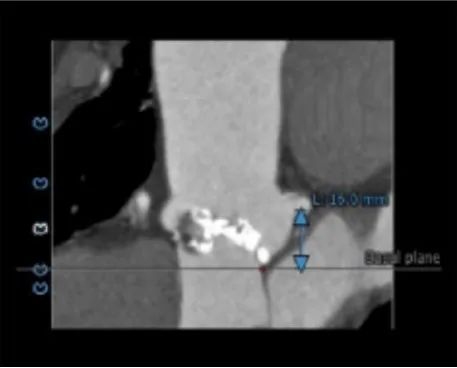

冠脉高度测量:

LEFT CORONARY

左冠开口高度16.0mm